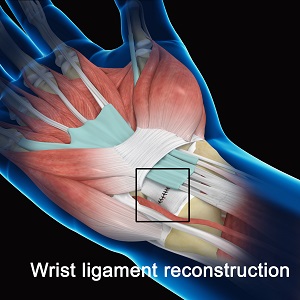

Know More - Wrist Ligament Reconstruction

Ligament reconstruction procedure can be performed as day surgery under local or general anesthesia.